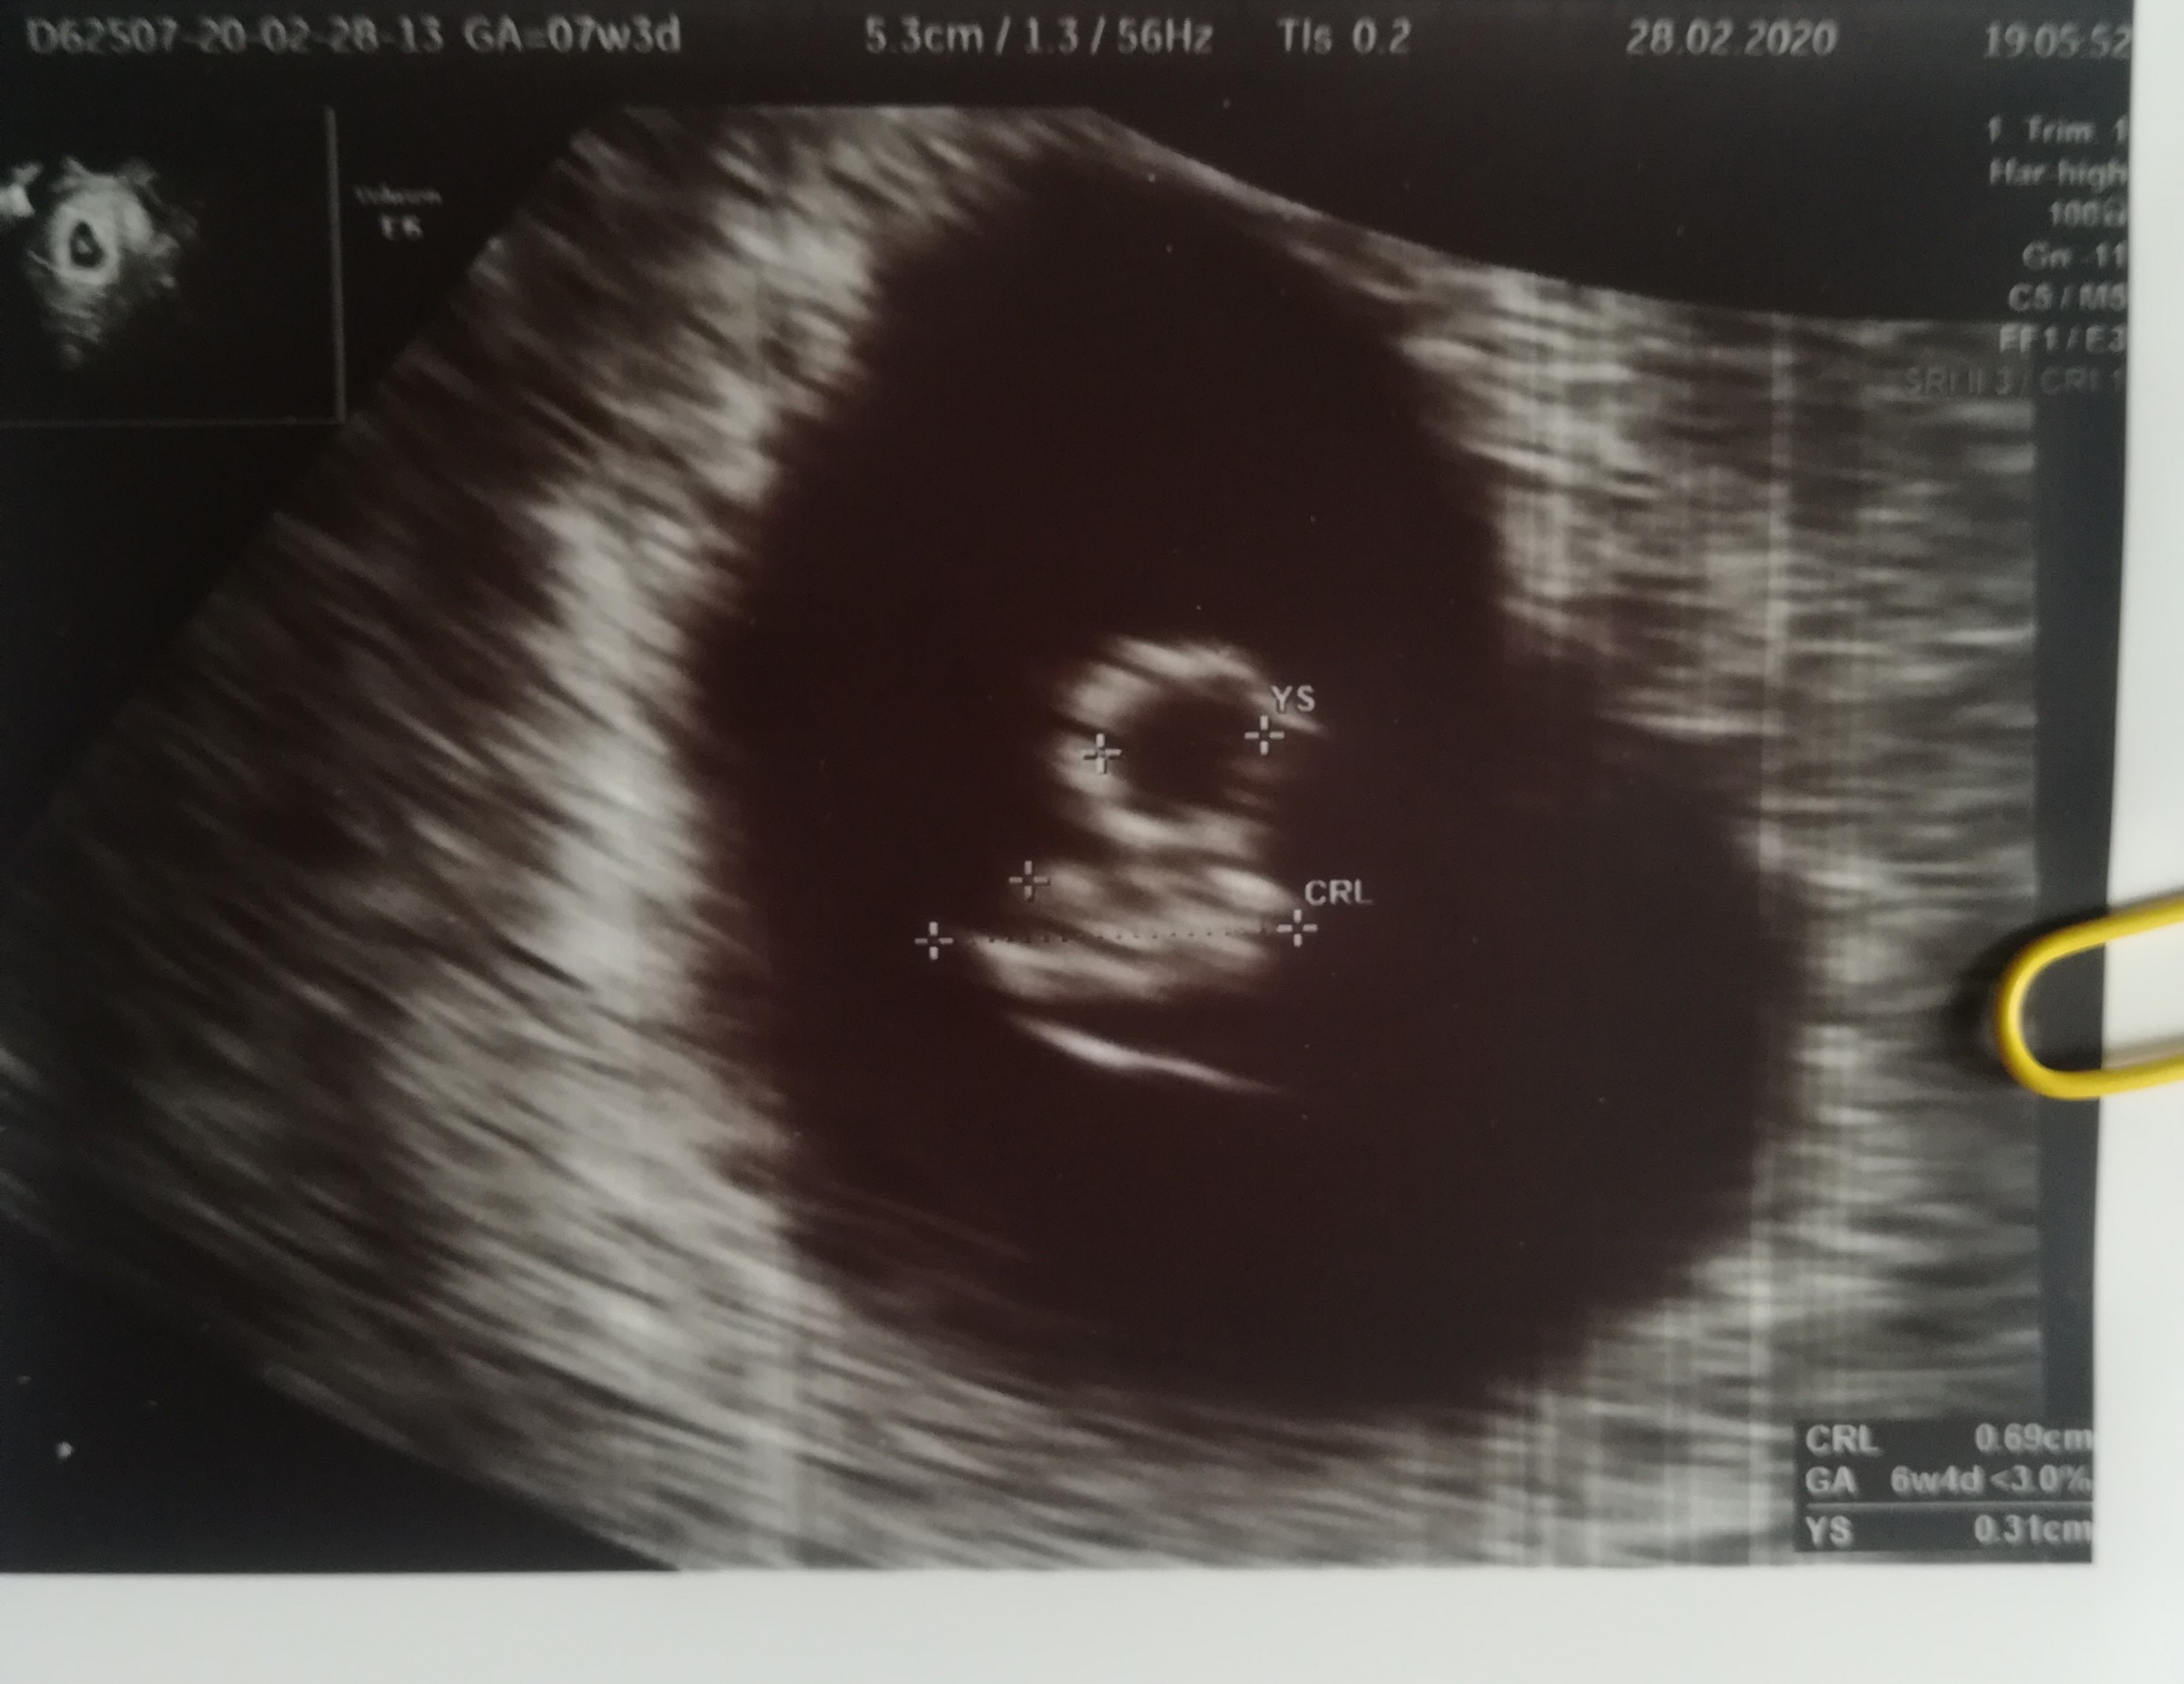

Ja w koncu wczoraj zobaczylam swoja Kruszyne ♥️ Om a wynik z Usg rozni sie o tydzień ale tego sie spodziewałam, bo mam dlugie cykle. Serduszka nie slyszalam, ale juz ładnie pulsuje. Moze uda sie w środę

Załączniki

• IMG_20200229_162507.jpg

IMG_20200229_162507.jpg

670,2 KB · Wyświetleń: 102